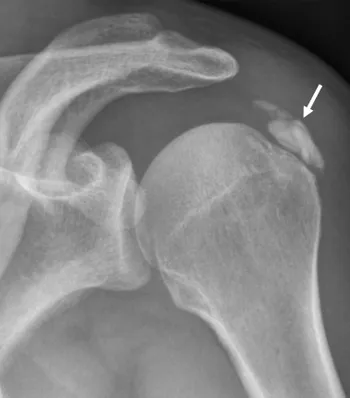

Pour des raisons mal connues (a priori indépendantes du type d’alimentation), des dépôts semblables à de la craie peuvent apparaître au sein des tendons de la coiffe des rotateurs.

- Elles sont responsables d’un conflit sous-acromial : lors de l’élévation du bras, les tendons calcifiés « accrochent » l’arche osseuse de l’acromion, entraînant une douleur aiguë.

- Elles augmentent le risque de rupture tendineuse : proportionnellement à leur taille, elles fragilisent les fibres du tendon.

Ces calcifications sont trop souvent banalisées car elles sont souvent indolores. Malheureusement ces calcifications désorganisent et détruisent à bas bruit les fibres des tendons au sein desquels elles se développent. Laisser grossir ces calcifications augmente le risque de rupture tendineuse lors d’un traumatisme ou d’un effort. Le traitement médical a l’inconvénient de calmer la douleur mais de laisser la calcification grossir à bas bruit. Dès que la taille de la calcification devient conséquente par rapport au tendon, la ponction lavage doit être proposée pour stopper son évolution.